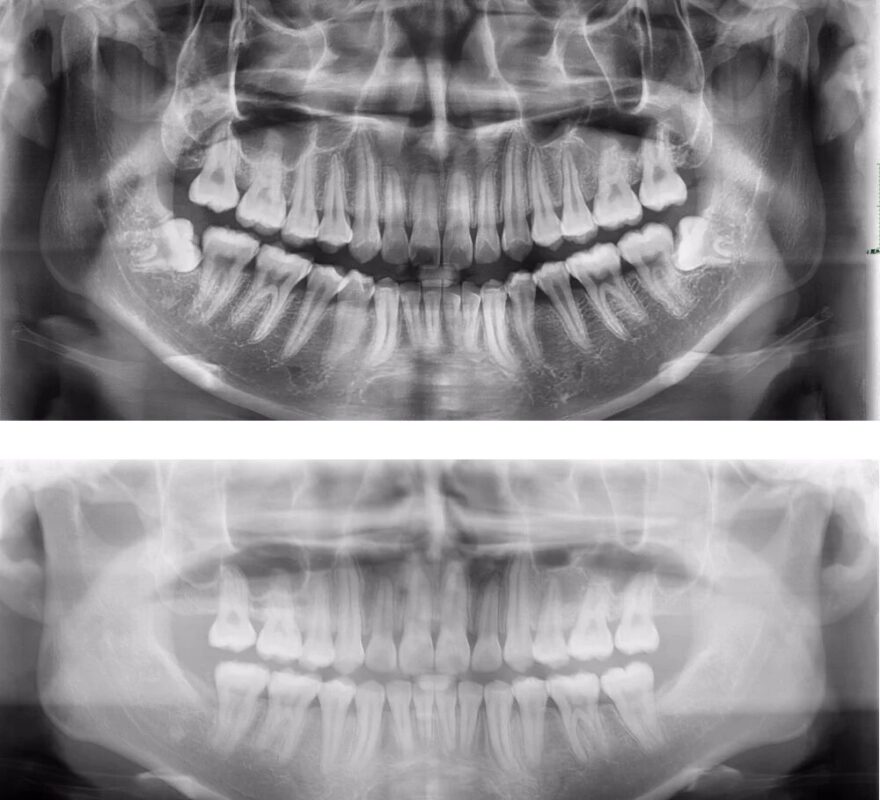

Nếu bạn muốn biết biết chính xác trường hợp giá niềng răng thưa cụ thể là bao nhiêu, hãy đến trực tiếp nha khoa để thăm khám. Tại đây, dựa trên các dữ liệu chụp X-quang, scan toàn hàm… nha sĩ sẽ có những phân tích và đưa ra câu trả lời chính xác nhất.